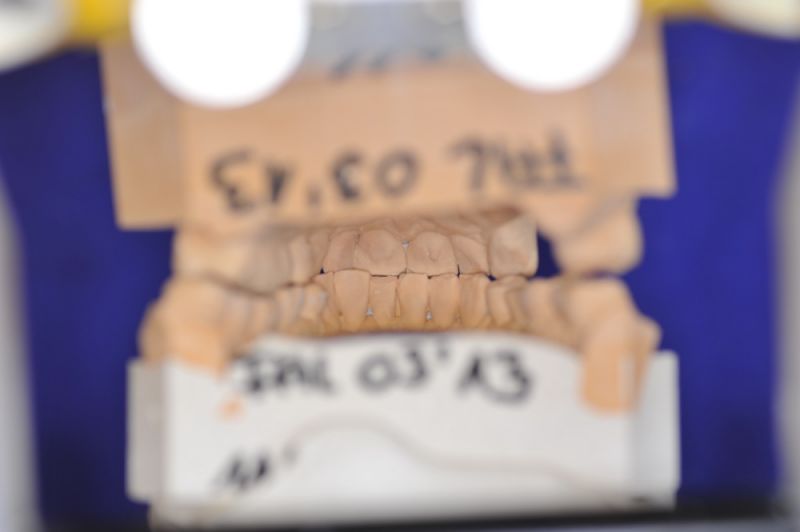

Über eine mehrjährige Phase wurden immer wieder Laborgefertigte Dauerprovisorien eingegliedert, weil vor einer abschließenden funktionstherapeutioschen Behandlung erst noch andere Problemzonen beseitigt werden mussten.